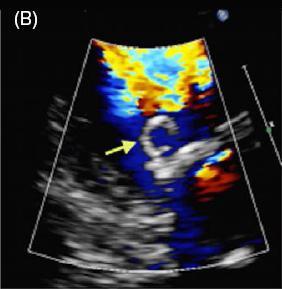

患者女,42 岁,以「急性视网膜动脉闭塞」病史就诊,既往无慢性疾病。经胸超声心动图检查发现二尖瓣后叶可见一囊状结构,可活动(图 A 和 B)。二维和实时三维经食管超声心动图检查显示一柔软的圆形结构附着于二尖瓣后叶,活动性良好(图 C ~ G)。主动脉弓、左心房、左心耳和左心室均正常。根据病变形态特征及超声表现,诊断为二尖瓣附瓣。其它影像学检查如 MRI、颈动脉多普勒超声均无异常。基于上述检查结果,考虑急性视网膜动脉闭塞为 AMVT 所致,建议外科手术切除二尖瓣附属组织,但是患者拒绝,选择随访观察。

图 B 彩色多普勒超声显示彩色血流进入囊状结构